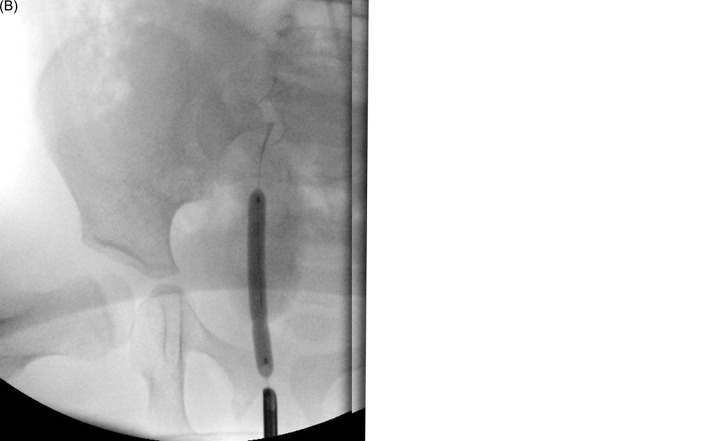

Objective: The aim was to evaluate the efficacy of high-pressure balloon dilatation (HPBD) for primary obstructive megaureter (POM) treatment in infants. Methods: The authors retrospectively reviewed medical records of 5 infants diagnosed with symptomatic or progressive POM and treated with HPBD between 2015 and 2022 in one hospital, analyzing changes in ureteral and anteroposterior pelvic diameters, Society for Fetal Urology grading, parenchymal thickness, differential renal function, complications, and subsequent surgical needs. Results: High-pressure balloon dilatation was performed on 5 patients, median age 5 months. No statistically significant changes were detected in ureteral diameter (median 11.0-7.0 mm, P = .125), anteroposterior diameters (median 21.5-18 mm, P= .255), parenchymal thickness (median 5.0-5.0 mm, P = .317), or differential renal function post-procedure. Follow-up was median 34 months. Three patients showed improvement in obstructive renogram findings. Complications were primarily related to guidewire insertion and double-J stent placement. Two patients, both younger than 6 months, required open ureteral reimplantation. Conclusion: High-pressure balloon dilatation serves as a minimally invasive approach for POM but is not universally effective, with a high complication rate and 40% of infants needing open surgery post HPBD.